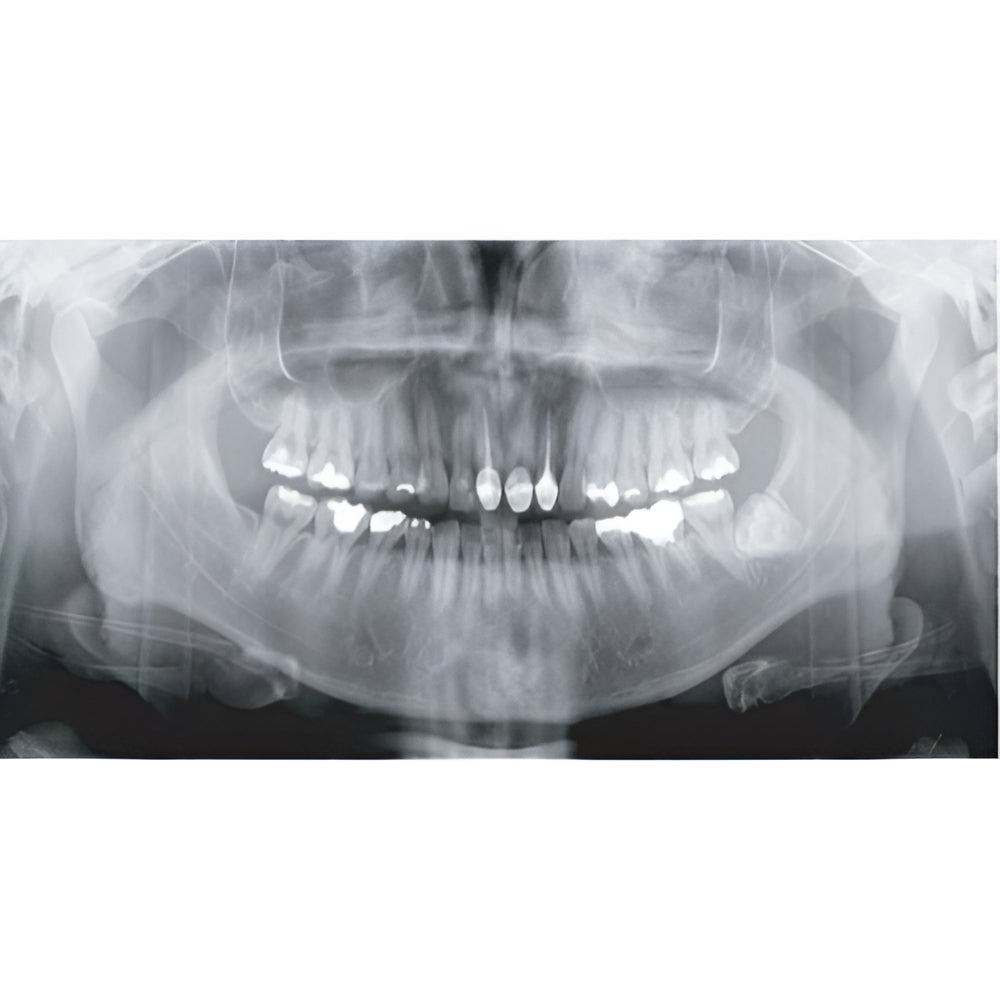

Genoray Papaya Plus Pan + CBCT (14x14 FOV)

Genoray Papaya Plus Pan + CBCT (14x14 FOV)

Papaya uses the CdTe sensor, which improves image quality while keeping radiation exposure to a minimum. The CdTe (Cadimium telluride) sensor overcomes the limitations of a CMOS sensor to always produce high quality images.

- Field Of View: 4x5, 7x7, 8x8, 14x8, 14x14

- Panoramic